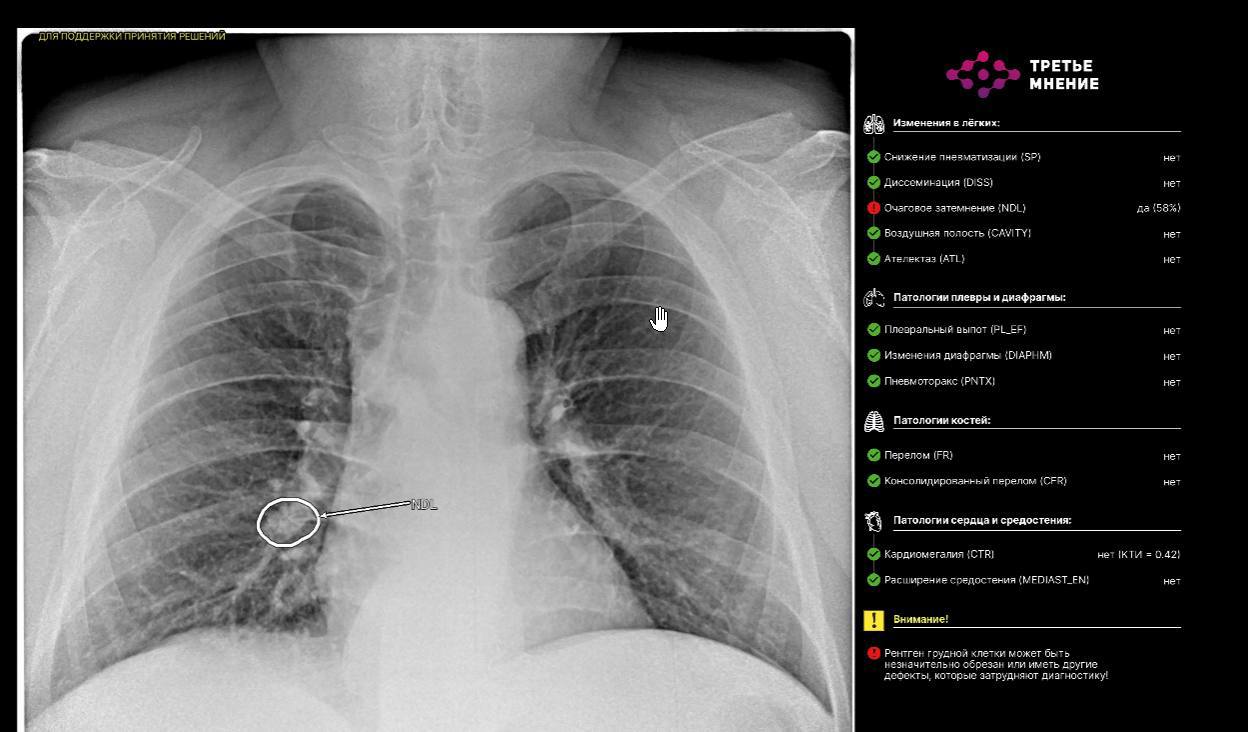

«Одной из ключевых особенностей новой системы является интегрированная в ЕРИС возможность использования технологии искусственного интеллекта, которая помогает врачу анализировать изображения, выявлять патологии и акцентировать внимание на участках, требующих детального рассмотрения. Это нововведение значительно расширяет возможности диагностики и повышает шансы на более раннее выявление заболеваний», — подчеркнул начальник Департамента здравоохранения Томской области Роберт Фидаров.